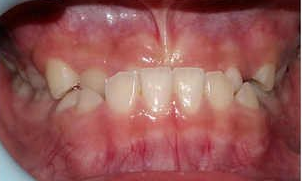

治疗前                        治疗后

儿童错合畸形早期矫治是阻断影响儿童颌骨、牙齿正常发育的因素,促进颌面部正常发育,降低II期矫正的难度,减少II期矫正的时间,甚至不需要II期矫正。让孩子早期获得自信,绽放灿烂笑容。

术前→术后